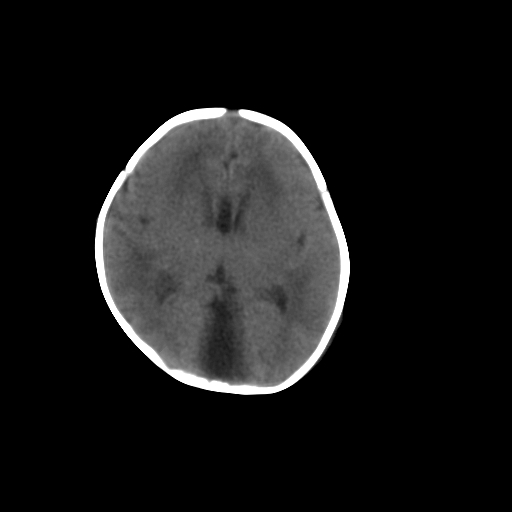

标题: PED1017:女,3天,足月顺产,出生后精神反应弱2小时。

女,3天,足月顺产,出生后精神反应弱2小时。

应该是大枕大池

依据:

1、低密度影由中线向两侧小脑表面延伸达岩锥

2、无明显占位效应

鉴别:

1、枕大池蛛网膜囊肿,常引起邻近颅骨的吸收和膨隆,枕大池蛛网膜囊肿可使四脑室前移位,伴病变以上脑室扩大。

2、dandy-walker综合征以脑积水和颅高压征常见,ct将其分为两型:

1.典型:第四脑室极度扩张或后颅凹巨大囊肿与第四脑室呈宽口相通,小脑蚓部缺如,合并脑积水。

2.变异型:第四脑室上部相对正常,可见袋状憩室从下髓帆发出,其大小、形态不一,小脑谿加宽,下蚓部发育不全、上蚓部相对正常,一般无脑积水

本例无巨大囊肿与第四脑室相通,小脑蚓部无缺如或发育不全,故不考虑

1)考虑hie。2)枕部颅骨内板下方类似囊状脑脊液样低密度影,鉴别于蛛网膜囊肿与巨大枕大池之间。